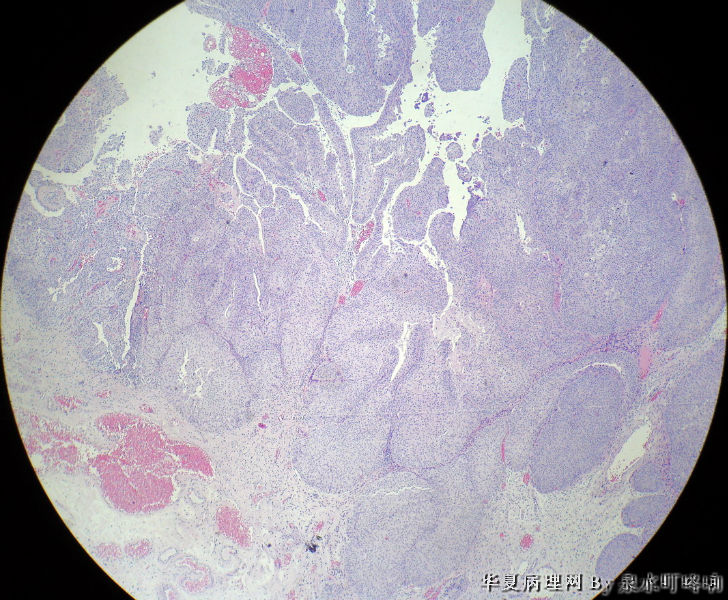

膀胱肿物

膀胱肿物图3

名称:图3

描述:3

男,76岁,血尿一个月,发现膀胱肿物,行切除术,肿物位于右侧膀胱后外侧壁,约1.5×1.5×1.5厘米。

大体:灰白肿物一个,大小约2×1.1×0.9厘米,切面灰白,质中。

尿路上皮癌,低级别。

低级别非浸润性乳头状尿路上皮癌

(膀胱)非浸润性乳头状尿路上皮癌,低级别

低级别尿路上皮癌。至于浸润的问题还请楼主仔细观察切片,总感觉那种推进式的生长模式有浸润的嫌疑,临床上浸润与否治疗方式是不一样的。

Dx: High grade papillary urothelial carcinoma because: 1. nuclear chromasia (fig 13) and coarse chromatin. 2, almost all nuclei have prominent  nucleoli. 3, Nuclear pleomorphism (some nuclei are three times larger than smaller ones). 4. Nuclear membrane irregularity. 5. mitosis can be seen far away from the basement membrane. 6. a good portion of the neoplastic cells loss orientation that should be perpendicular to the basement membrane. 7. Low power view shows papillary branching and fusion. 8. patient's age

However, this should be the low end of the spectrum of high grade urothelial carcinoma. Careful search might reveal some focal microinvasion.or urothelial carcinoma in situ.